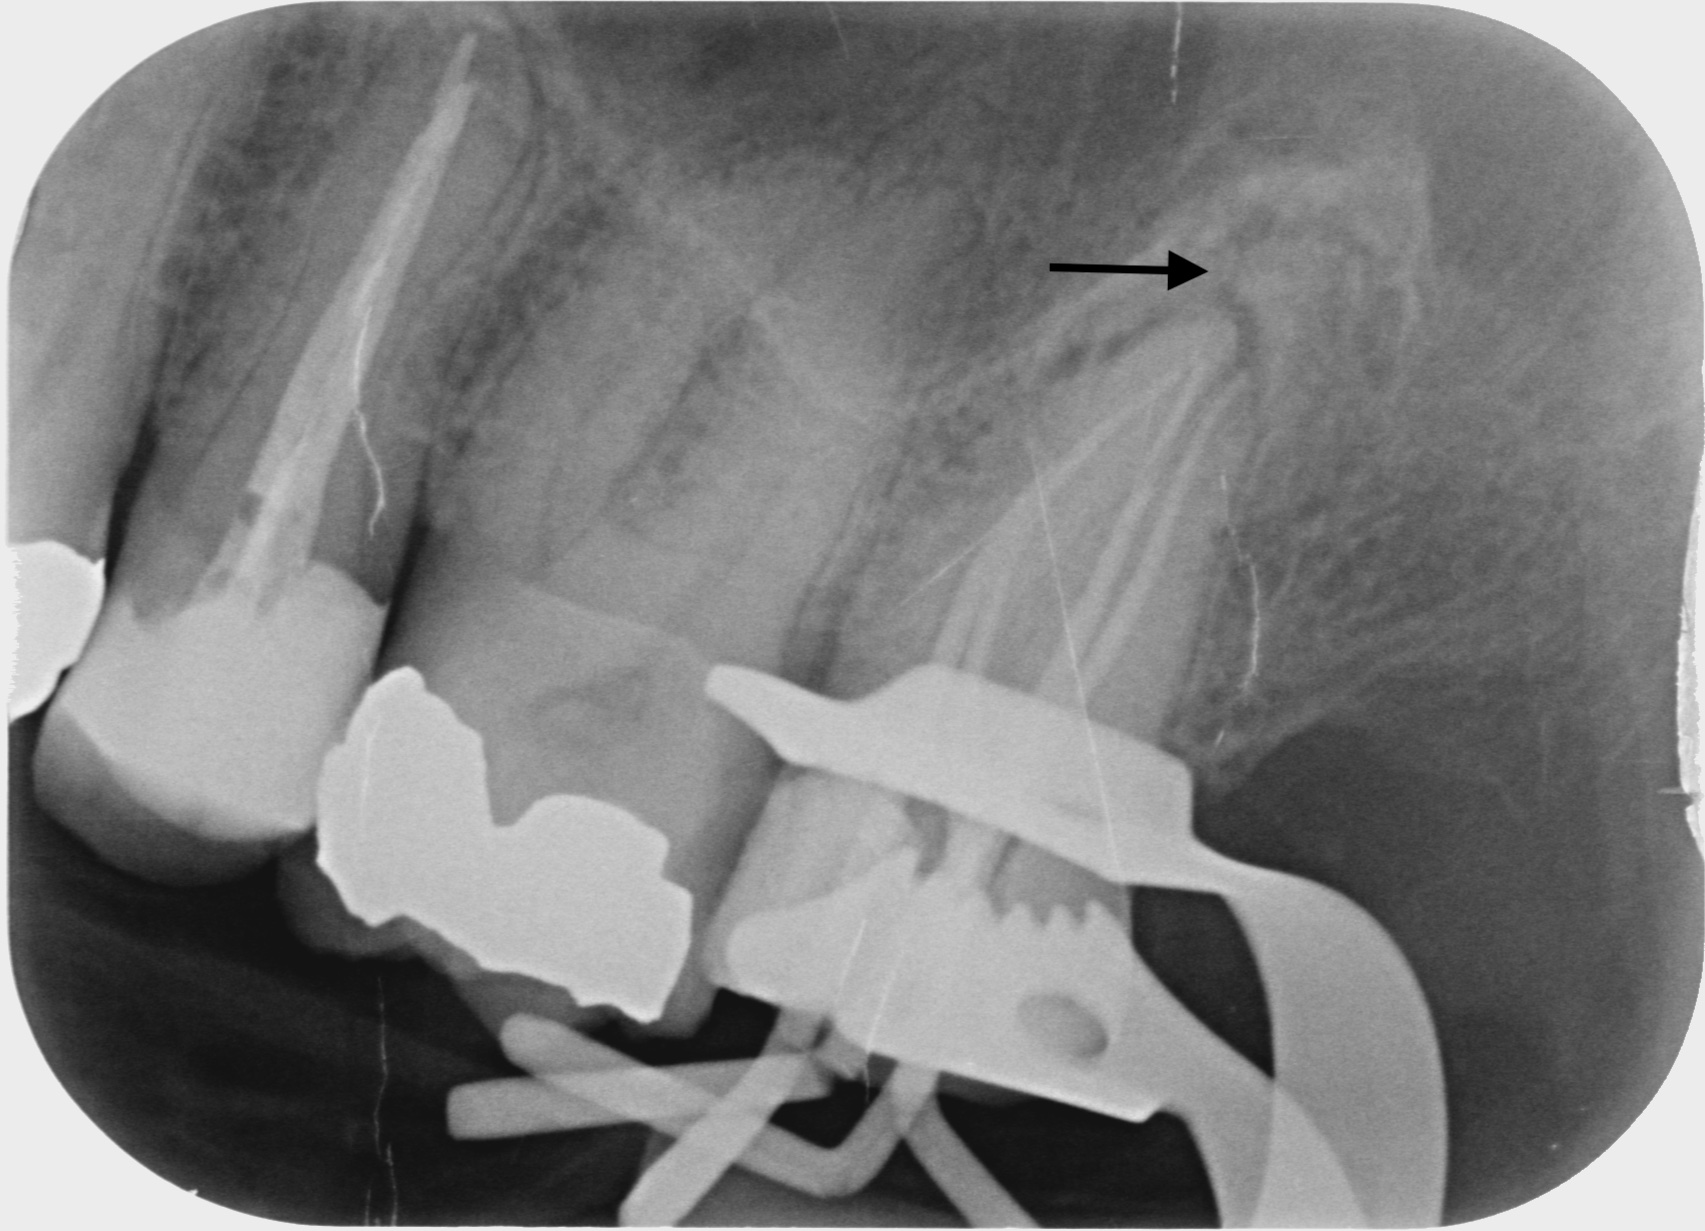

Fallbeispiele

Zum Vergrössern klicken